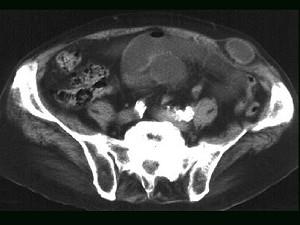

问题 女,60岁,反复左下腹隐痛约20年,伴包块外突2年余,站立或增加腹压后有一包块外凸,质地较软,平卧时消失且腹痛缓减,CT检查如图,最可能的诊断是 ( )

选项 A、腹壁转移瘤 B、盲肠炎 C、半月线疝 D、腹壁脂肪瘤 E、肠梗阻

答案 C